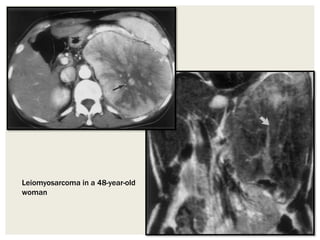

Leiomyosarcomas

• Retroperitoneum is the most common extra uterine site for

leiomyosarcoma.

• Arise from smooth muscle within arteries, veins or bowel. The

most frequent site is the IVC (50%), and they are more

common in women.

• Metastases to liver and lung are common when the tumour is

Radiographic features

• Like other sarcomas, imaging findings are non-specific.

Retroperitoneal leiomyosarcomas tend to develop massive

cystic degeneration. Unlike other sarcomas, fat and

calcification are not typically present.

Leiomyosarcoma in a 48-year-old

woman